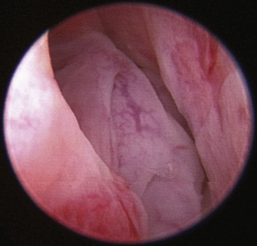

Normal turbinates have a smooth, pink-to-white surface and a spatial alignment that provides channels for the passage of air. The color varies and appears tan in the caudal nasal cavity. Turbinates come in different shapes and sizes, but the surface should be smooth. Ethmoid turbinates in the caudal nasal cavity will have a characteristic stippled or corrugated appearance (Figures 19-13 through 19-16). Ulcerations or various proliferations of the mucosa are indicative of disease. These changes are typically diffuse and accompanied by a lot of mucus. Mucus can be thin to purulent. Copious amounts can be flushed out of the nasal cavity to allow better visibility. The specific disease is determined by biopsy. After full examination of the nasal cavity, run the scope along the floor of the nasal sinus to the level of the choanae. Keeping the scope pointed in a ventral medial direction prevents inadvertent trauma or penetration of the cribriform plate. The index finger of the free hand can be used to follow the scope as it moves caudally over the hard palate; the surgeon can then palpate the scope through the soft palate when it moves into the nasopharynx. Some force is needed to complete this procedure and may result in increased bleeding.

Figure 19-15 Normal canine nasal turbinate mucosa.

image

Figure 19-16 Normal canine ethmoid turbinate.